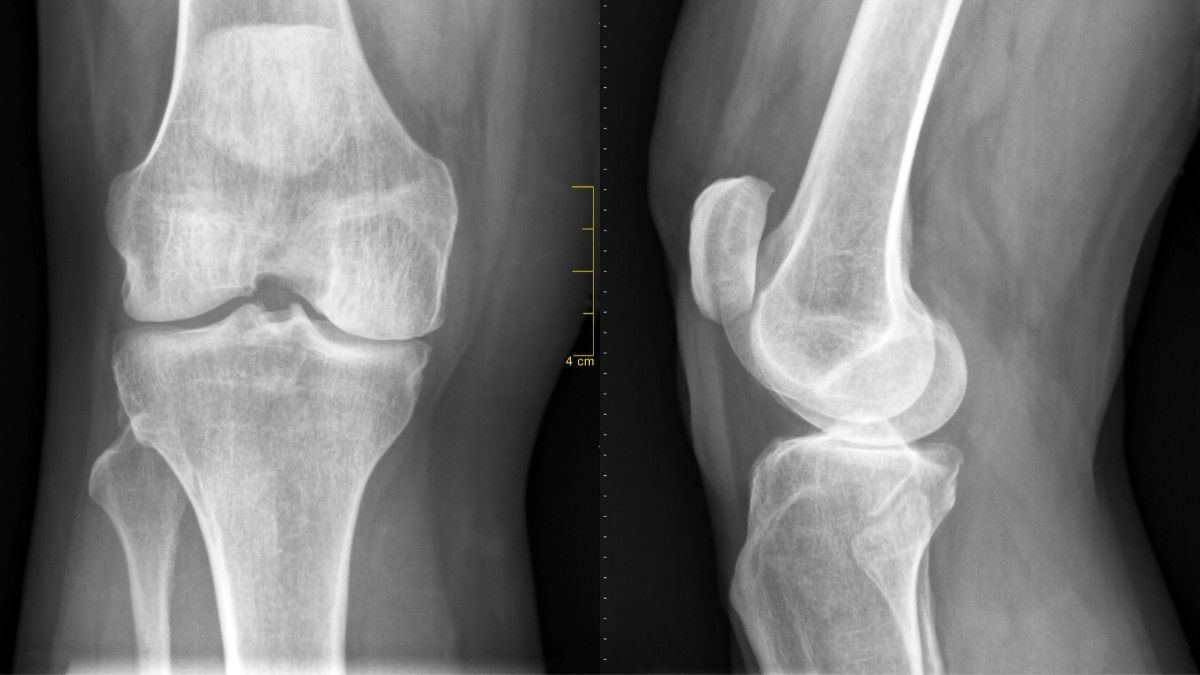

Osteoartritis

Osteoartritis terjadi ketika tulang rawan mengalami penipisan seiring berjalannya waktu. Padahal, tulang rawan berfungsi sebagai bantalan tulang.

Semakin tipis bantalan tulang, semakin besar risiko gesekan yang terjadi. Hal itu dapat menyebabkan kerusakan tulang. Osteoartritis atau radang sendi bisa terjadi di berbagai tempat, namun kondisi ini umum menyerang lutut, pinggul, tulang belakang, dan juga tangan.

Ketika mengalami osteoartritis, tulang akan mengalami pembengkakan dan membuat penderitanya sulit menggerakkan sendi.